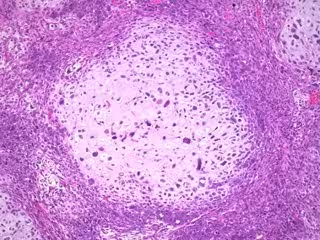

Las pacientes con un tipo de cáncer de mama llamado HER2-positivo tienen menos probabilidades de sobrevivir si su tratamiento inicial no consigue erradicar el tumor por completo y tienen altos niveles de células inmunitarias llamadas linfocitos infiltrantes del tumor en la enfermedad residual. Ahora, los investigadores han identificado cómo ciertas células inmunitarias contribuyen a una peor supervivencia en pacientes con cáncer de mama HER2-positivo.

La doctora Federica Miglietta, de la Universidad de Padua y oncóloga médica del Istituto Oncologico Veneto, en Italia, ha explicado en la 13 Conferencia Europea sobre el Cáncer de Mama que, normalmente, los linfocitos infiltrantes de tumores (LIT) ayudan al sistema inmunitario del organismo a combatir las células cancerosas. Sin embargo, en el caso de este tipo de cáncer de mama, impulsado por los receptores del factor de crecimiento epidérmico humano 2 (HER2) en la superficie de las células cancerosas, los LIT posteriores al tratamiento parecían ser contraproducentes si quedaba alguna enfermedad después de que las pacientes hubieran recibido quimioterapia y terapia anti-HER2 antes de la cirugía (lo que se conoce como "tratamiento neoadyuvante").

Los investigadores del cáncer se han interesado cada vez más por el papel del sistema inmunitario en el cáncer y por las formas de aprovecharlo para combatir la enfermedad. Por ello, la doctora Miglietta y sus colegas analizaron los datos de 295 pacientes con cáncer de mama HER2-positivo que habían sido tratadas en tres centros italianos entre 2001 y 2021: el Istituto Oncologico Veneto, la Azienda Unit Sanitaria Locale di Reggio Emilia y el IRCCS Humanitas Research Hospital - Humanitas Cancer Center. El 66% de los pacientes (195) tenían enfermedad residual tras el tratamiento neoadyuvante. Se disponía de información sobre la cantidad de enfermedad residual ("carga de cáncer residual") y de LIT en los tumores residuales de 180 y 159 pacientes, respectivamente.

"Evaluamos los niveles de LIT en las muestras quirúrgicas de la enfermedad residual tras el tratamiento neoadyuvante y también valoramos su papel pronóstico --explica--. Descubrimos que la supervivencia global de las pacientes con cáncer de mama HER2-positivo, que tenían LIT en más del 15% de la superficie de su tumor, era significativamente más corta que la de las pacientes con niveles más bajos de LIT".

"Sabemos que el tumor está rodeado por el llamado microambiente tumoral, como un ecosistema complejo en el que las células tumorales y las células normales del paciente, incluidas las inmunitarias, se afectan y moldean mutuamente. Nuestros resultados sugieren que el microambiente inmunitario de la enfermedad residual, tras la exposición a la quimioterapia y a la terapia dirigida contra el HER2, fomenta el crecimiento de las células cancerosas en lugar de luchar contra ellas, y este fenómeno parece afectar profundamente a la historia natural de la enfermedad", afirma Miglietta.